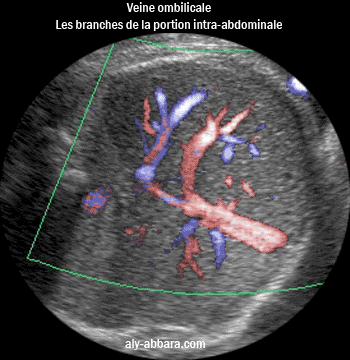

Coupe échographique montrant le trajet parcouru et les branches de la veine ombilicale

à l'intérieur de la cavité abdominale (le sinus porte et le canal veineux d'Arantius "ductus veineux")

Ftus de

35 SA